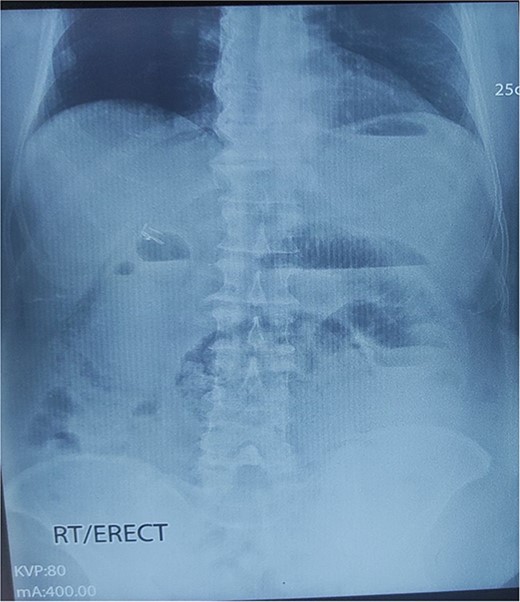

An abdominal X-ray showed distended small bowel loops with multiple air-fluid levels (Fig. 1). A CT scan of the abdomen and pelvis revealed multiple distended jejunal loops (maximum diameter 5.6 cm) clustered in the left upper quadrant, with proximal and distal narrowing suggestive of a closed-loop obstruction, consistent with a paraduodenal hernia (Fig. 2).

X-ray abdomen erect showing dilated small bowel loop with multiple air-fluid levels.